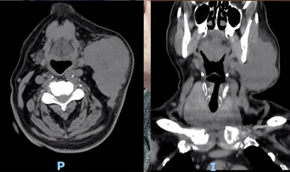

Inicialmente, foi realizada uma citologia aspirativa que descrevia “Aspetos compatíveis com carcinoma de fenótipo neuroendócrino, favorecendo-se neste contexto um carcinoma de células de Merkel, embora não se possa excluir um tumor neuroendócrino de outra localização”. Fez também uma Tomografia Computorizada (TC) cervical sem contraste, por suposta alergia ao mesmo, que identificou “massa sólida com 92 x 75 x 46 mm, sem seguro plano de clivagem com a face anterior do músculo esternocleidomastoideu, nem com o ramo ascendente da mandíbula esquerda” (Figs. 4 e 5).

Figs. 4 e 5: TC cervical sem contraste (corte axial e coronal) - Massa cervical esquerda com provável extensão muscular e ao ramo da mandíbula.